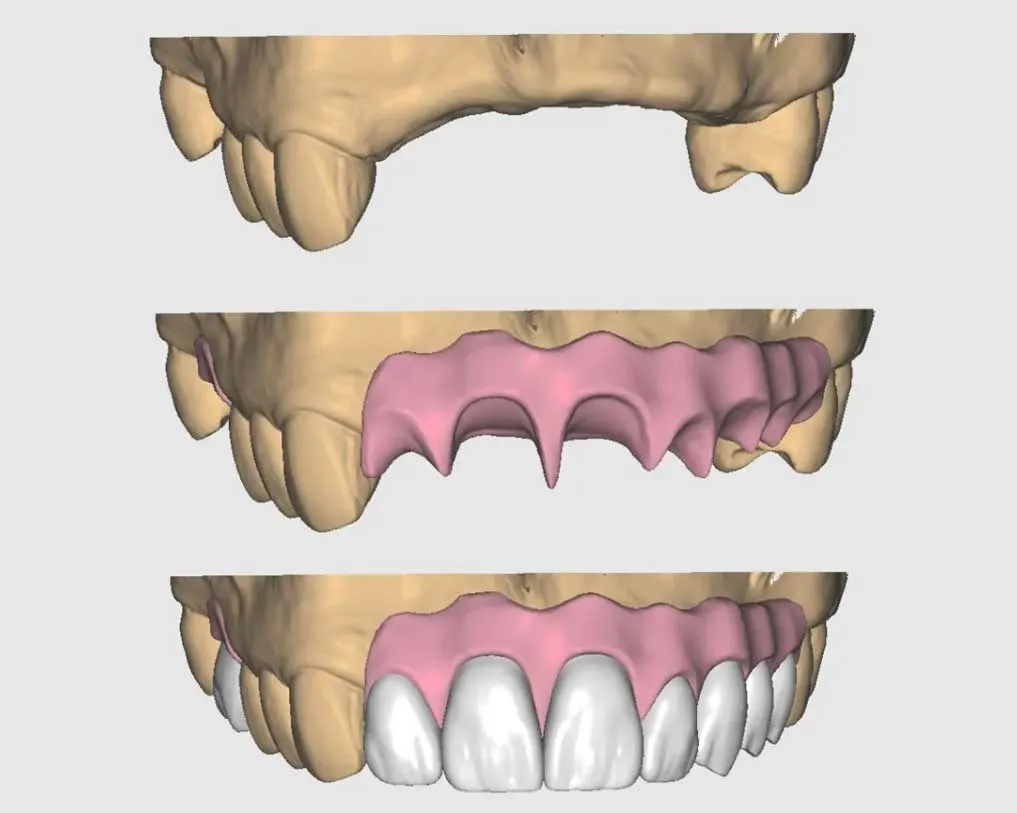

ENCERADO DIGITAL

Una excelente forma de planificar la sonrisa de sus pacientes. A partir del encerado podemos crear prototipo mock up, provisionales, guías para carillas, guías quirúrgicas entre otros procedimientos más.